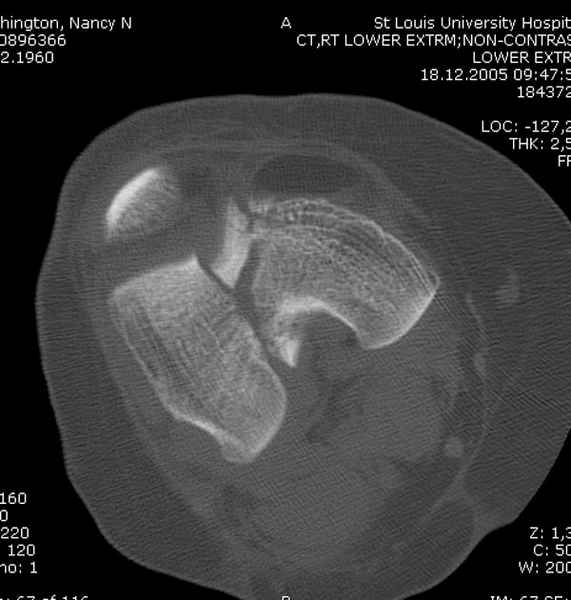

При наличии различных имплантов, любые варианты: слева (полу) открытым - мининвазивным, а справа закрытым интрамедуллярным методом, его считаем более чем приемлемым для фиксации данных переломов.

Проксимальная и дистальная блокировка, независимо от техники введения штифта, ретроградно или антеградно, гарантирует сращение сегментарных переломов бедра без укорочения. Штифты диаметром 12 мм с блокировкой сверху и вниз двумя шурупами выдерживают вес 75 кг больного, что позволяет раннюю профилактику контрактур.

Главное в лечении сегментарных переломов - необходима осторожность при рассверливании канала, продвижение гибкого сверло через сегмент проводят без сверления, толканием, а то были случаи, когда весь сегмент крутился вместе со сверлом.